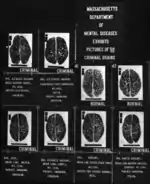

Cesare Lombrosos and his Italian School of criminology argued against the utlitarian school by assuming that deviants and criminals break social norms and laws due to atavistic traits. In other words, they believed that these people are not as highly advanced in the evolutionary process as normally functioning members of society. The Italian School also believed that these atavistic traits are indicated by physical, biological indicators of a person such as body type or the shape of the face. These theorists believed that deviants are not flexible individuals; criminal tendencies stem from biological factors, and thus they believed that punishment would not work since biological determinants on crime would be more or less fate. Therefore, if punishment would not work, then neutralization of the deviant was necessary. The theorists in the Italian School believed that institutions such as mental hospitals, lifetime imprisonment, or the death sentence would neutralize the deviant and thus make the society fit for the normal people to live safely.